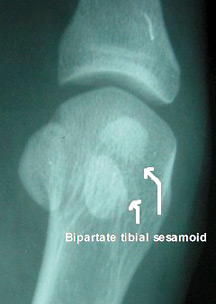

A comparison X-ray can sometimes be helpful in determining if a fracture is present. If the bipartite appearance is present bilaterally, there is a greater chance that the sesamoid is truly bipartite and not fractured. Clues of fracture include irregular and jagged appearance of the separated fragments.

One could make the diagnosis with examination and correlating history; however, imaging with plain films is important to rule out fracture and the treatment will be different if there is an occult fracture. Standing AP and lateral forefoot films will demonstrate bipartite sesamoids and OA, but a better view is usually obtained with an axial skyline view of the sesamoids with the MTPJ in dorsiflexion.

Figure 3: Bipartite appearance of the sesamoids.